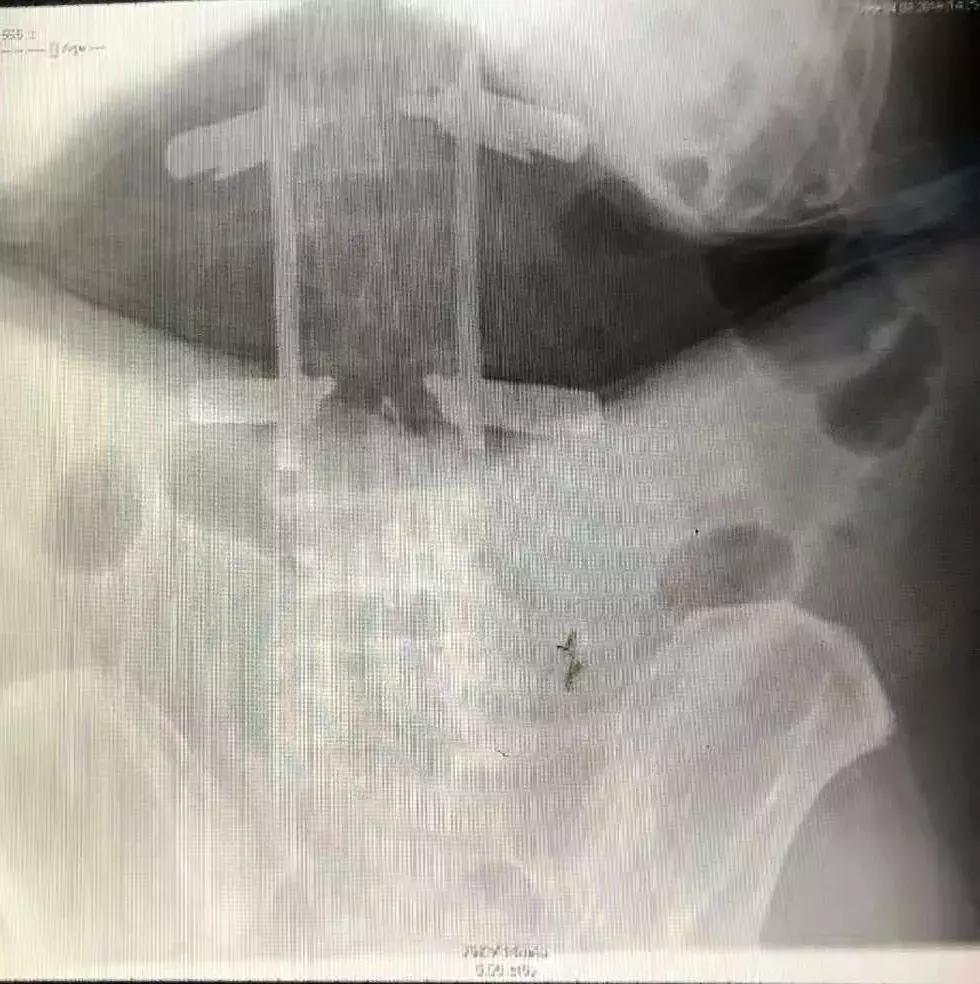

术后正侧位压缩椎体高度恢复,螺钉位置精确